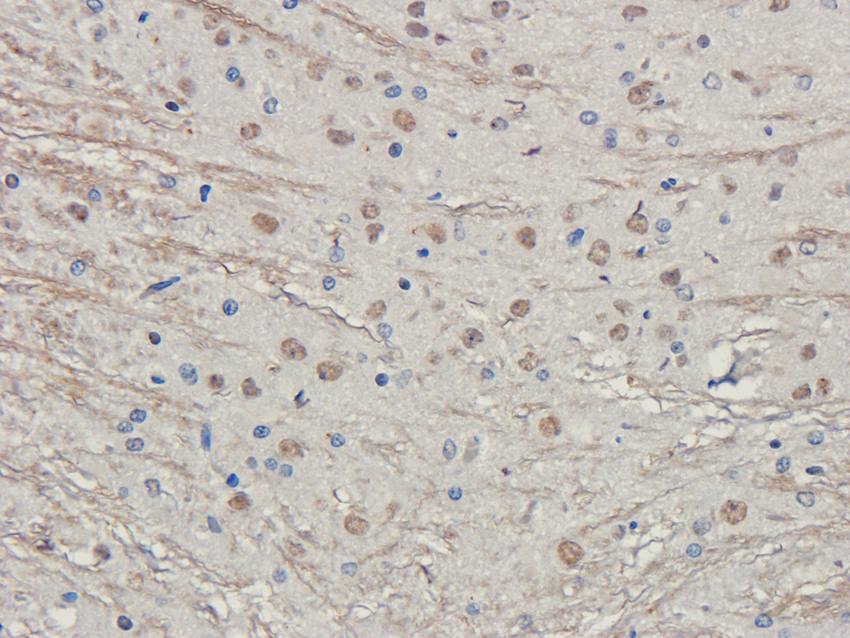

应用稀释比例:IF/ICC: 1:50-400, WB: 1:200-1000, IHC-P: 1:50-400